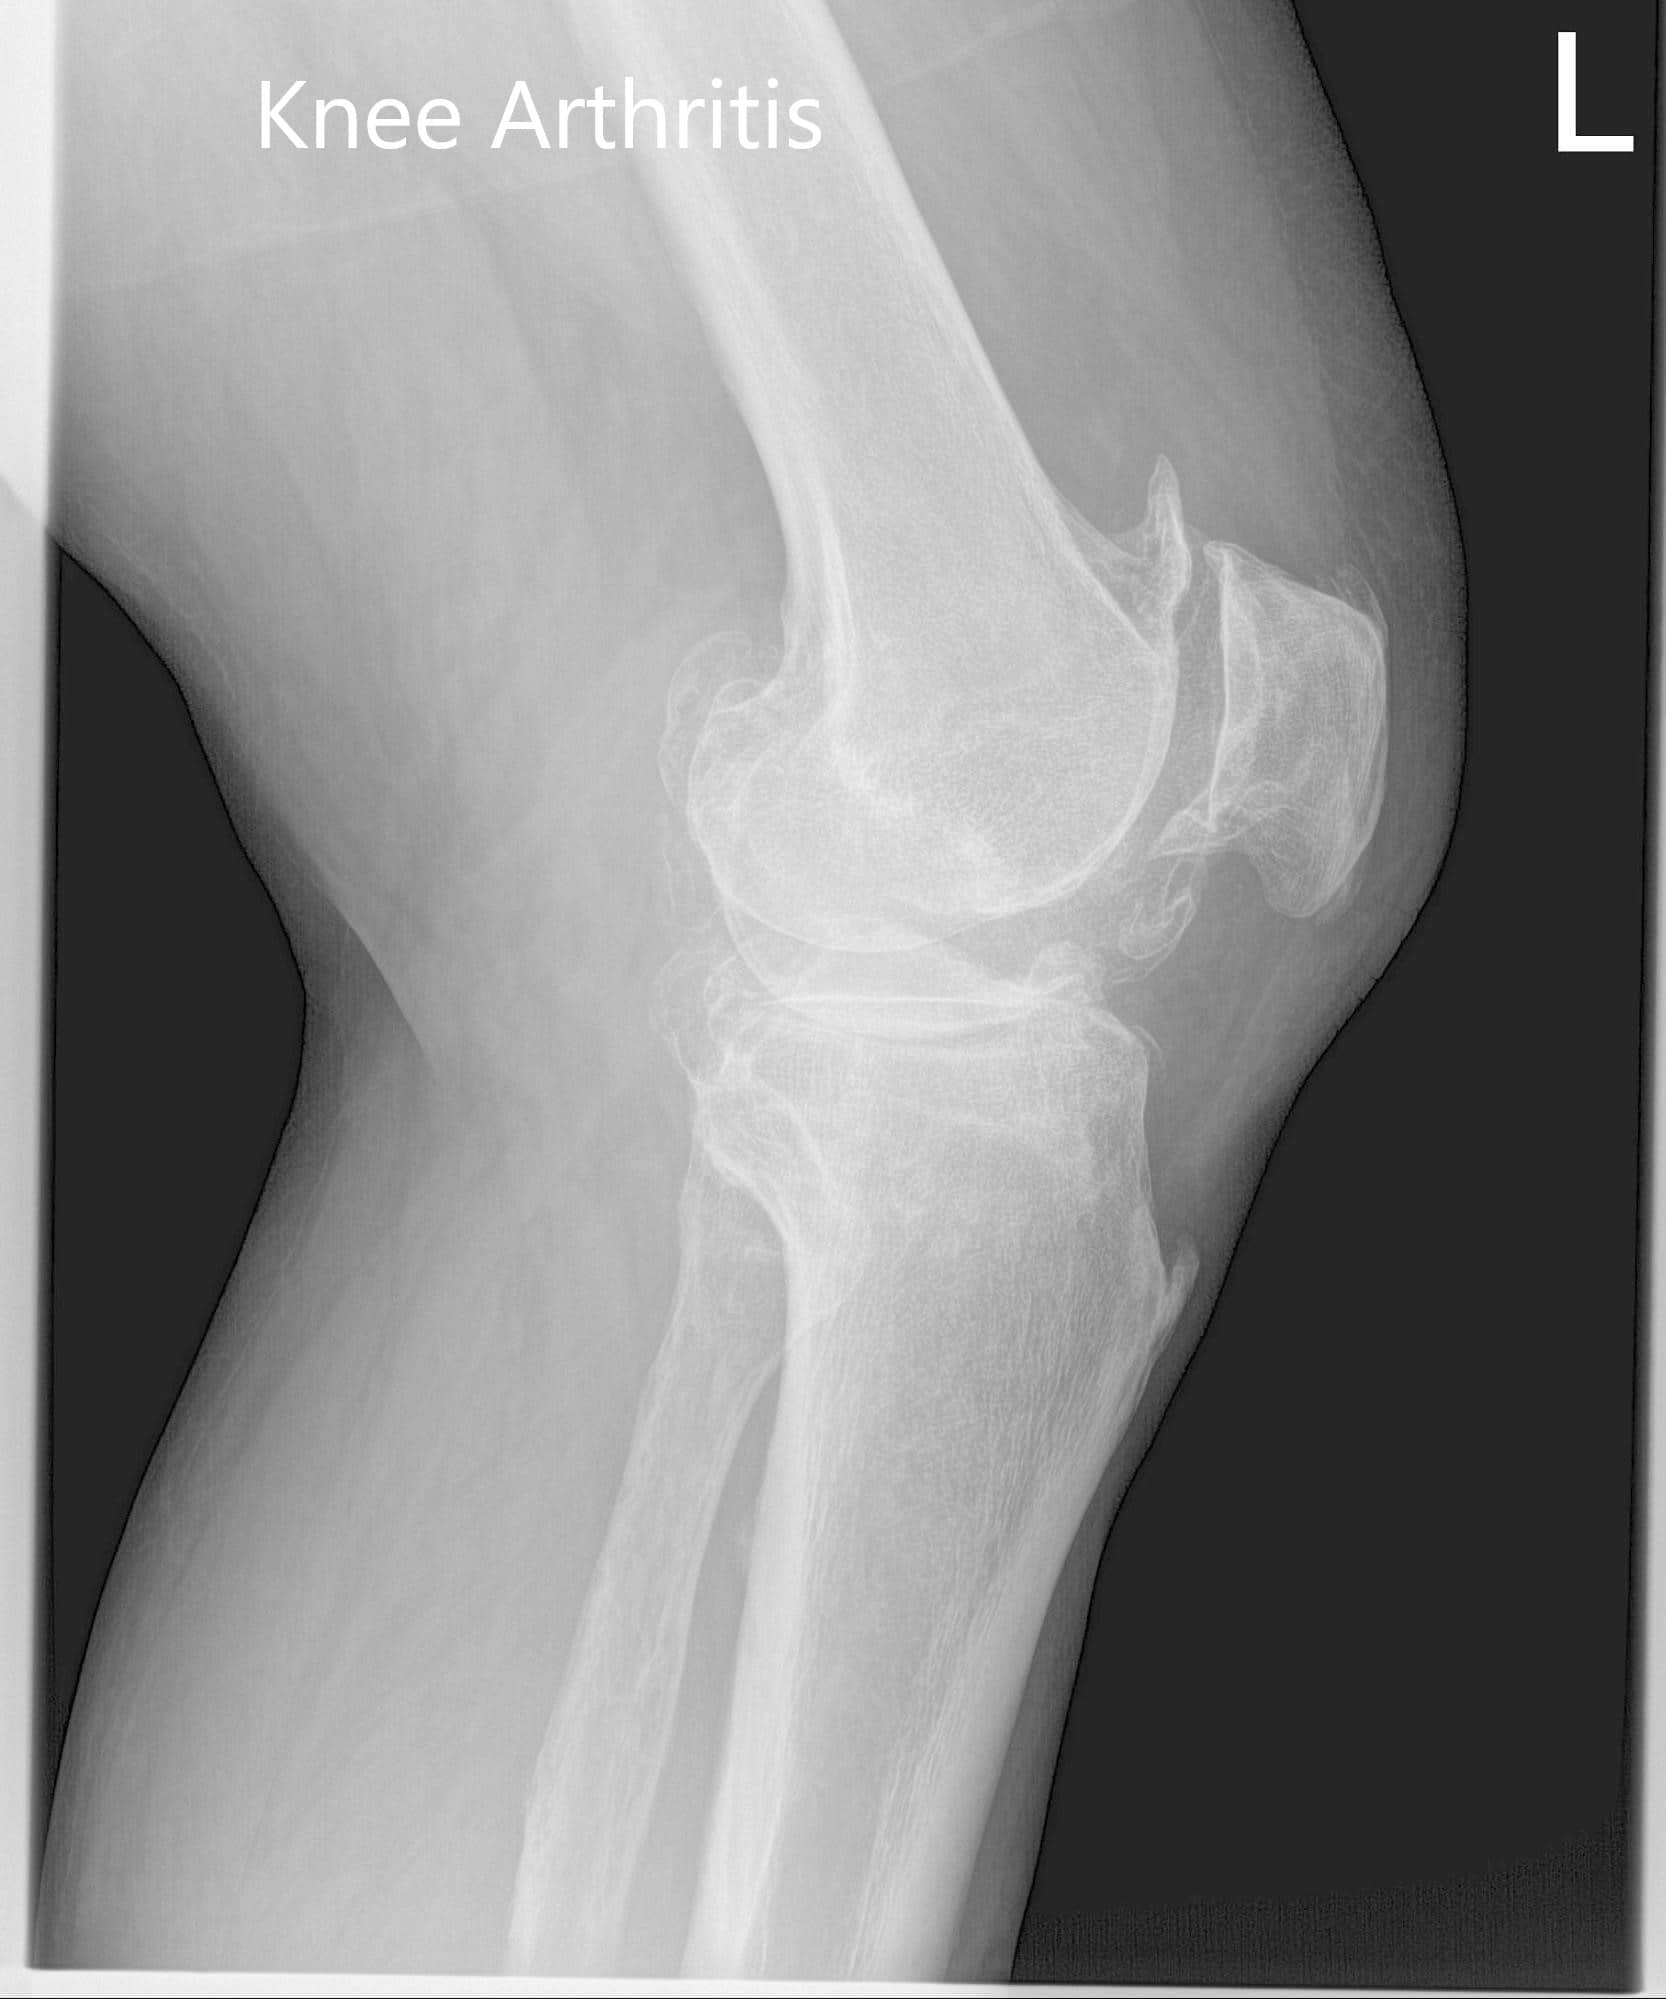

Considering his lifestyle limiting knee pain, various management options including both surgical and nonsurgical were discussed with him at length. He was considered a candidate for custom left knee total replacement. Risks, benefits and potential complications were discussed with him in detail. He agreed to the plan. Imaging studies revealed severe tricompartmental osteoarthritis of the left knee joint.

Preoperative X-ray of the left knee showing AP and lateral view of the knee with a skyline view of the patella.